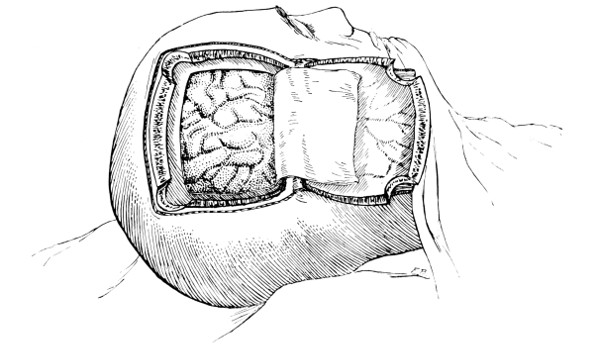

Fig. 19. Third Stage in the Formation of an Osteoplastic Flap. The dural flap turned down and the brain exposed. Note the relation of the scalp, bone, and dural incisions to one another.

Reference has already been made to the great importance of opening the dura in such a manner as to avoid injury to the underlying superficial cerebral vessels (see p. 19). It may be incised in a crucial manner or by flap-formation. Flaps are usually to be preferred if the surgeon desires to have the widest possible view of the brain surface. In the formation of the flap, advantage should be taken of the vessels that minister to its vitality. Thus, in the lateral region of the head, the base lies below, the middle meningeal artery supplying the flap. Under special circumstances, the blood-supply may be disregarded; the flap never sloughs, so far as my experience goes.

Considerable difficulty may be experienced in sewing up the dura—by reason of the bulging of the brain. How these difficulties may be overcome is dealt with on p. 236. The edges should be united by numerous fine silk sutures.

The[30] flap is replaced, care being taken that its lower or fractured edge does not injure the dura mater. The aponeurotic and subcutaneous tissues of the scalp-flap are sewn up in the manner stated on p. 16.